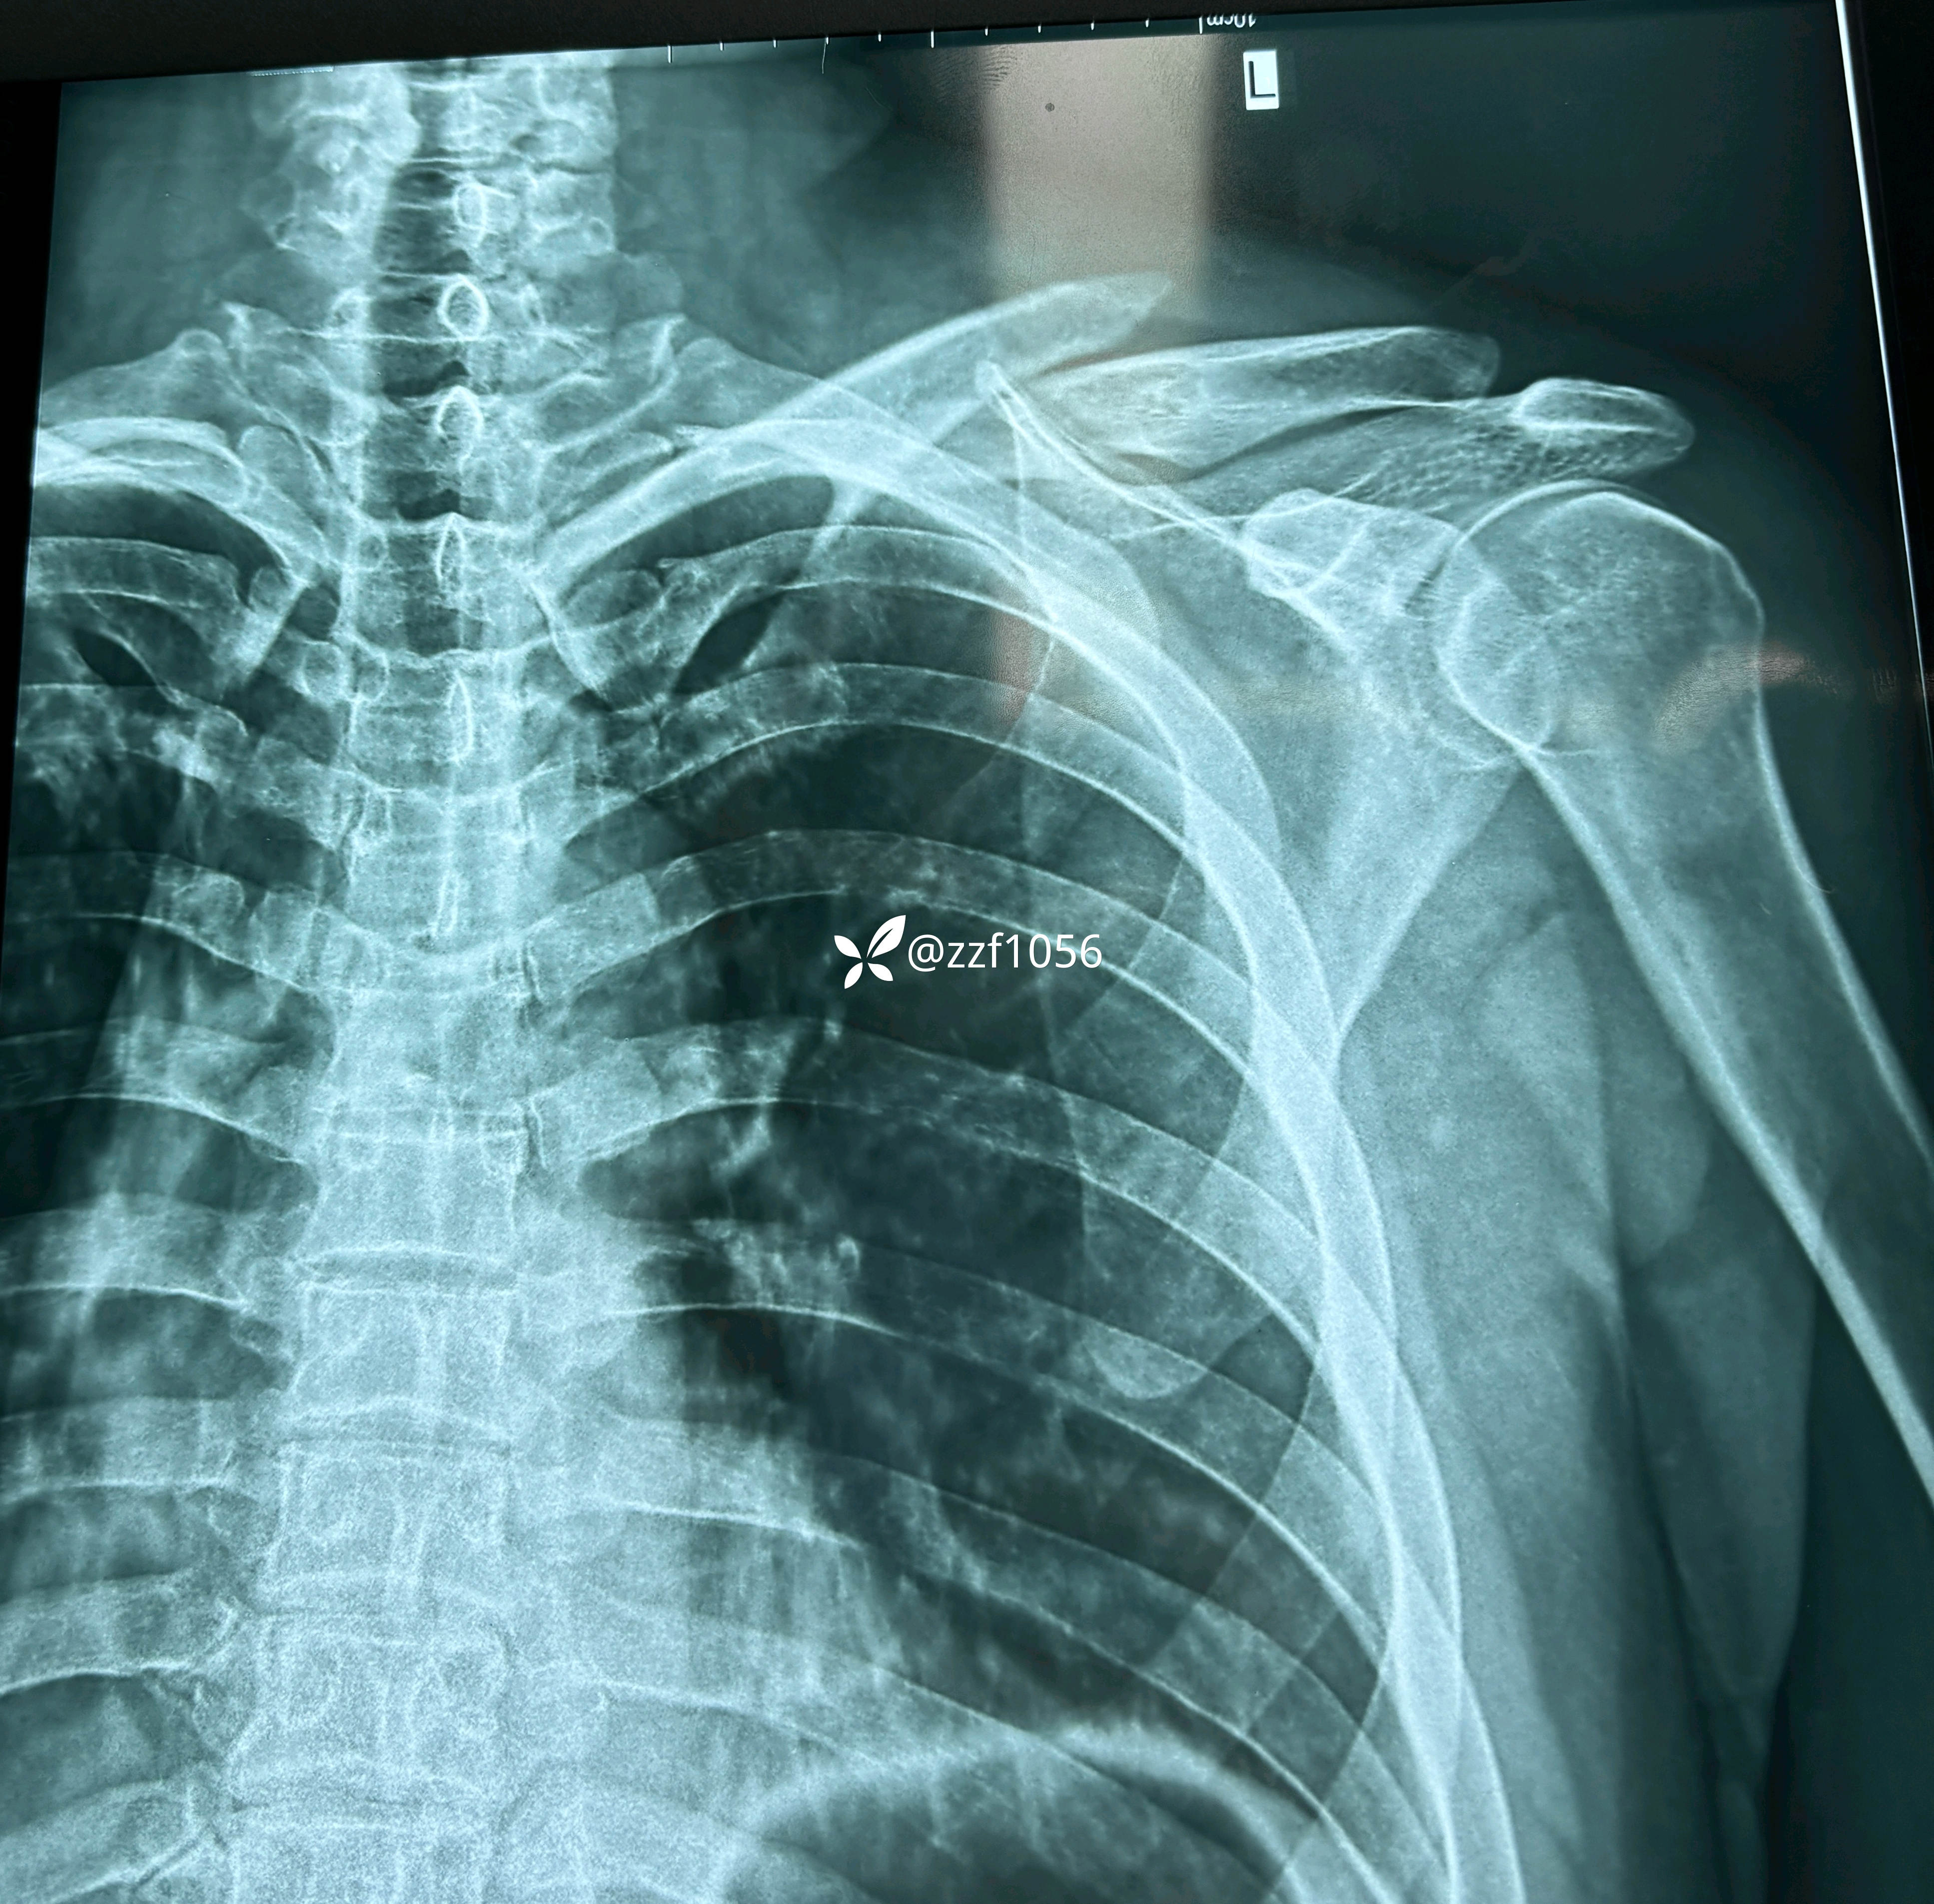

患者男性,34岁,摔伤左肩肿痛致左侧锁骨骨折在外院住院1天准备手术

术中作切口后探查未见皮神经,保护好骨膜,清理折端复位临时克氏针固定,后方蝶形骨块较大,nice结改2道钢丝捆扎,复位良好,取最长10孔钢板,貌似钢板有点短,远折端3枚锁定螺钉有效固定,近折端只有2枚螺钉有效固定,第3枚螺钉失效且后方仍有骨块微翘,无奈增加一枚钢丝适宜捆扎。